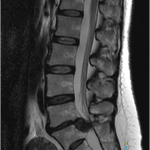

坐骨神経痛に限らず、痛みや身体の不調があると病院に行って検査を受けるのが当たり前のことだと思います。それは病気や身体の専門家としてお医者さんは国家資格として認められた職業だからです。その中でも坐骨神経痛のように脚の痛みやしびれなどがある場合は整形外科を受診することが通常です。整形外科に行くとまず初めにレントゲンで腰椎(腰の背骨)を撮影し骨に異常が無いかを確認します。そして次にMRIを行って脊髄の流れに異常がないか、椎間板が膨隆・突出して脊髄を圧迫していないかを確認します。

このような場合は椎間板ヘルニアと診断されるでしょう。飛び出した椎間板が脊髄を圧迫しています。